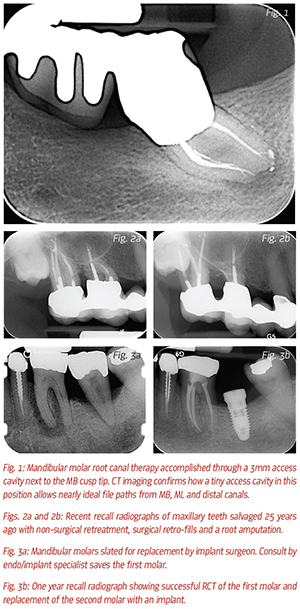

Root canal therapy can be done through remarkably

conservative access cavity preparations and it has never been

easier to treat root canal systems to their full apical and lateral

extents (Fig. 1). An experienced endodontist can,

through conventional and surgical means, definitively

resolve disease states inside teeth without destroying the

structural integrity of the abutment (Figs. 2a-b).

Conclusion

The time has come for endodontists to think of

themselves as understructure specialists, rather than dentists

with a specialty certificate who only do non-surgical

re-treatment procedure that many GPs assume they can

do themselves. If you want to be a specialist, be special

(Figs. 3a-b).